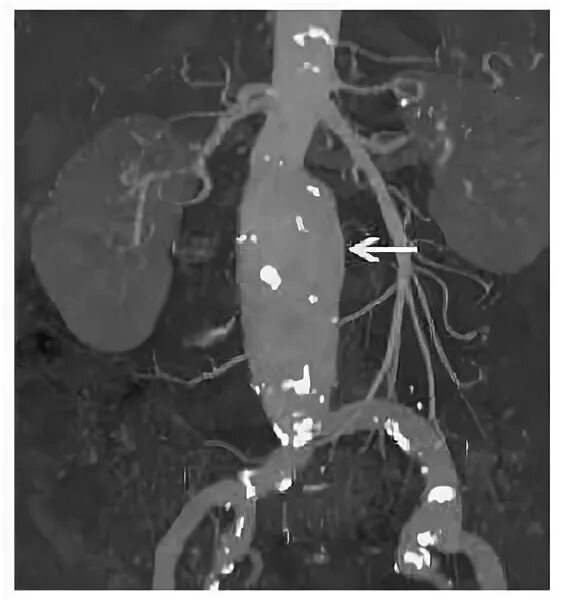

Кальциноз брюшного отдела